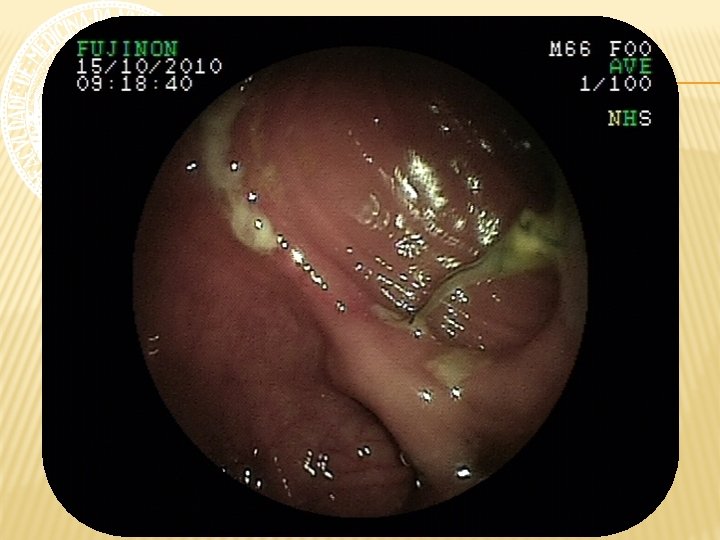

ENTEROSCOPIA RETRÓGRADA Nota-se em reto médio, a 15 cm da borda anal, LESÃO ELEVADA, pediculada, com superfície ulcerada, recoberta por fibrina e hematina, de aspecto subepitelial, medindo cerca de 4 cm de diâmetro. A 20 cm da borda anal, presença de ANASTOMOSE ileorretal, com algumas pequenas ulcerações, recobertas por delgada camada de fibrina, com fios de sutura, sem sinais de sangramento ativo e/ou recente. Íleo percorrido por cerca de 40 cm, não se observando alterações da mucosa. Realizada aplicação de endoloop, seguida de POLIPECTOMIA, sem intercorrências.